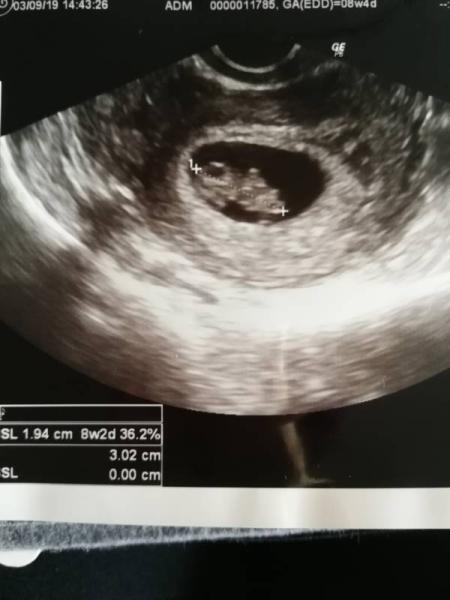

Ja, wir hatten gestern auch Termin. Eigentlich bin ich 9+3, aber nach der Größe unseres kleinen Schatzes war er gestern schon 9+5 (also heute 9+6) Laut Frau Doktor ist alles soweit in Ordnung. Heute habe ich einen Termin zum Ersttrimesterscreening am 24.9. ausgemacht. Der nächste Termin bei meiner Gyn ist dann am 1.10. Kann es jetzt schon kaum erwarten, das kleine tanzen zu sehen Gestern hat es ein paar Mal kurz gezuckt

Das Bild noch

Bild zu